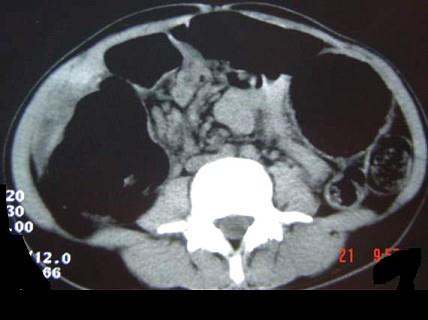

问题 女,30岁,便秘、腹痛腹胀多年,CT检查如图,最可能的诊断是 ( )

选项 A、结肠肠扭转 B、结肠肠栓塞 C、先天性巨结肠 D、结肠肠套叠 E、结肠肠梗阻

答案 C